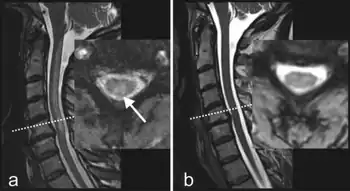

MRI-T2 images may reveal increased signal within the white matter of the spinal cord, predominantly in the posterior columns and possibly in the spinothalamic tracts.

Individual suffering from subacute combined degeneration of spinal cord a) before and b) after cobalamin substitution/treatment

Therapy with vitamin B12 results in partial to full recovery where SACD has been caused by vitamin B12 deficiency, depending on the duration and extent of neurodegeneration.